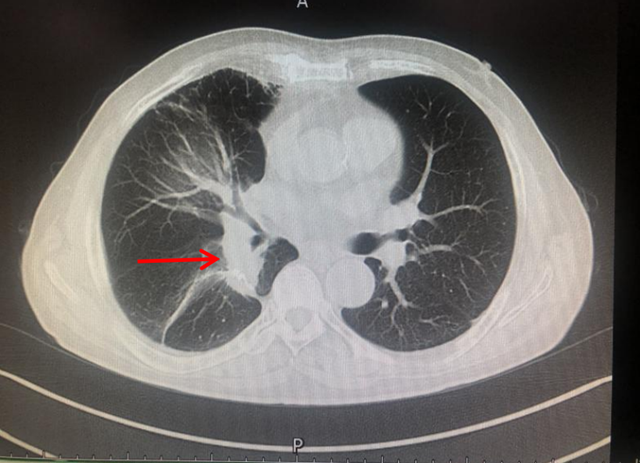

2014年,古稀之年的刘先生,因心累气促,在外院检查发现右肺肿瘤,经手术切除后确诊为肺腺癌早期,术后规律复查。2017年肿瘤复发,并伴有多处淋巴结及肺内转移,诊断为晚期肺癌。

拒绝行放化疗后,刘先生病情进行性加重……外院医生多次沟通后,刘先生又接受了放射治疗,但放疗结束仅5个月肿瘤又长大了。

此时,仍拒绝行全身化疗的刘先生慕名找到西南医科大学附属中医医院肿瘤·血液病科学科主任廖大忠教授,结合患者实际情况及意愿,予以PD-1抑制剂帕博利珠单抗免疫治疗,治疗期间配合中医药增效解毒,患者全程耐受,不良反应逐渐减轻至消失,同时肿瘤缩小。

此后,刘先生一直坚持在肿瘤·血液病科(忠山院区)行免疫联合中医药治疗,从2019年3月至今,已4年时间,刘先生除偶尔咳嗽外,无其他不适。谁能想到这样一个年逾八旬、精神矍铄的老人竟然是位晚期肺癌患者呢?